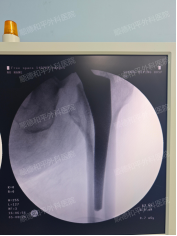

手术当日,副主任俞泉带领团队凭借丰富的临床经验和精湛的微创技术,有条不紊地开展人工股骨头置换手术。术中严格遵循精准操作原则,避开重要血管神经,优化手术流程,整个手术仅用1小时便顺利完成,出血量少,患者生命体征始终保持平稳。

“手术很成功,现在感觉怎么样?”术后第二天,俞泉副主任医师查房时,陈阿姨兴奋地回应:“刀口疼明显减轻了,比术前舒服太多!”在专业康复护理团队的指导下,陈阿姨开始进行床上功能康复训练,从简单的关节活动到肌力锻炼,逐步恢复髋关节功能。